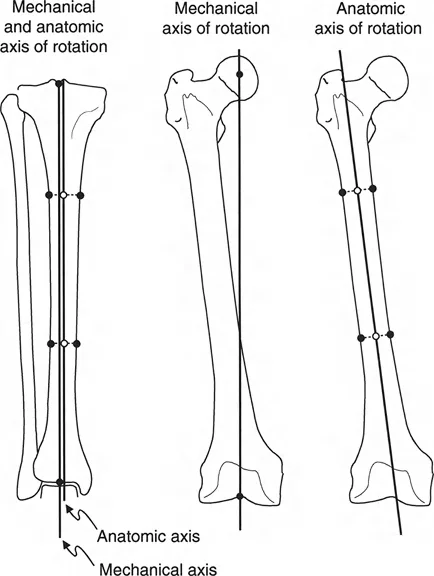

PATHOANATOMY AND BIOMECHANICS

Understanding the biomechanical forces at play is essential for executing this procedure successfully. The normal distal radius physis grows symmetrically, maintaining a neutral to slight volar tilt and a standard radial inclination. In dyschondrosteosis, the Vickers ligament acts as a rigid volar-ulnar tether.

As the dorsal and radial aspects of the physis continue to grow, the tethered volar-ulnar corner acts as a hinge. This results in:

* Volar and Ulnar Angulation: The articular surface of the radius tilts progressively volar and ulnar.

* Carpal Subsidence: The lunate, tethered by the Vickers ligament, subsides proximally into the widened radioulnar space, creating a V-shaped carpal configuration.

* Ulnar Impaction: The distal ulna, unaffected by the radial growth arrest, continues to grow, resulting in positive ulnar variance and dorsal prominence.